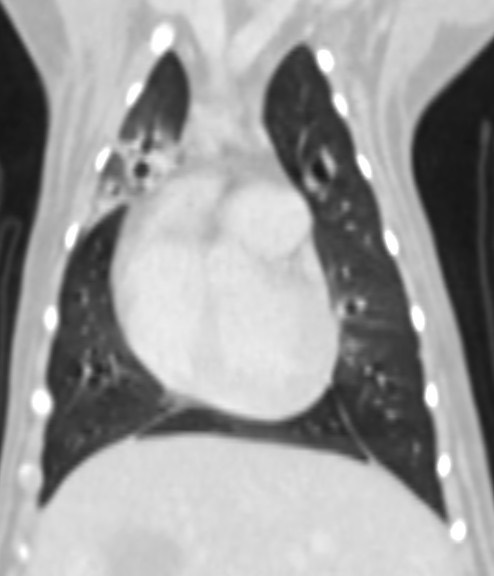

長達5個月的慢性咳嗽就診 反覆支氣管肺炎的狗狗Ainy,因為對藥物的反應時好時壞,

建議用電腦斷層掃瞄與氣管支氣管內視鏡探查評估病因與治療方式

電腦斷層檢查排除結構上異常引起的發炎,支氣管鏡探查發現病灶處有多量異常黏液樣分泌物,

於是進行支氣管肺泡灌洗(broncho-alveolar lavage, BAL)取得檢體,染色下細胞抹片可見發炎細胞跟桿菌,細菌培養結果為綠膿桿菌,對一般抗生素無效。

於是使用有效的抗生素治療6周後,追蹤到現在近半年都穩定囉